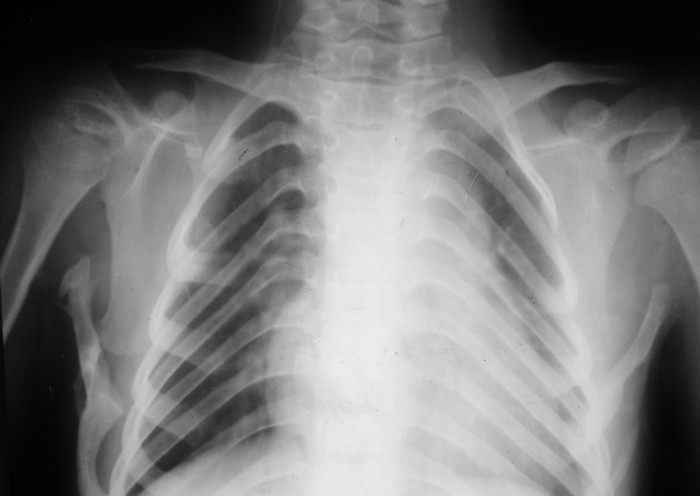

Врожденная аномалия, множественные экзостозы

Жалобы: на нарушение функции верхних конечностей: невозможность движения в обеих правых плечевых и локтевых суставах; ограничение движений в шейном отделе позвоночника, наличие опухолевидных множественных образований на спине и пробам бедре.

Анамнез заболевания: со слов матери появлению множественных опухолевидных образований на спине предшествовал массаж воротниковой зоны в 4 года. Консультирован в Областной детской больнице и Областном онкодиспансере. В декабре 2010 г. после падения с велосипеда ушиб левый локтевой сустав, a в январе вторичное падение с велосипеда с ушибом правого локтевого сустава, после чего пациент отметил постепенное ухудшение функции обеих верхних конечностей вплоть до резкого ограничения объема движений в обеих плечевых и локтевых суставах.

Место болезни: при осмотре определяется - вынужденное положение верхних конечностей в плечевых и локтевых суставах, множественные опухолеподобные образования вдоль позвоночника и по наружной поверхности верхней трети левой бедренной кости округлой формы, с четкими контурами, неподвижные, безболезненные, каменистой плотности. приводяще-отводящая контрактура в обеих плечевых суставах, сгибательно-разгибательная контрактура в обеих локтевых суставах с сохранение про- и супинационных движений. Объем движений в пальцах кисти и лучезапястных суставах в полном объеме без ограничений, безболезненный.

Диагноз: врожденная аномалия развития шейного отдела позвоночника с резким нарушением функции в плечевых и локтевых суставах, множественных костно-хрящевые экзостозы, оссифицирующий миозит.

рентгенограммы

это fibrodysplasia ossificans progressiva, генетически обусловленная прогрессирующая метаплазия соединительной и мышечной ткани в костную. Лечится (вернее, тормозится) консервативно, после попыток оперативного лечения и после травм - прогрессирует.